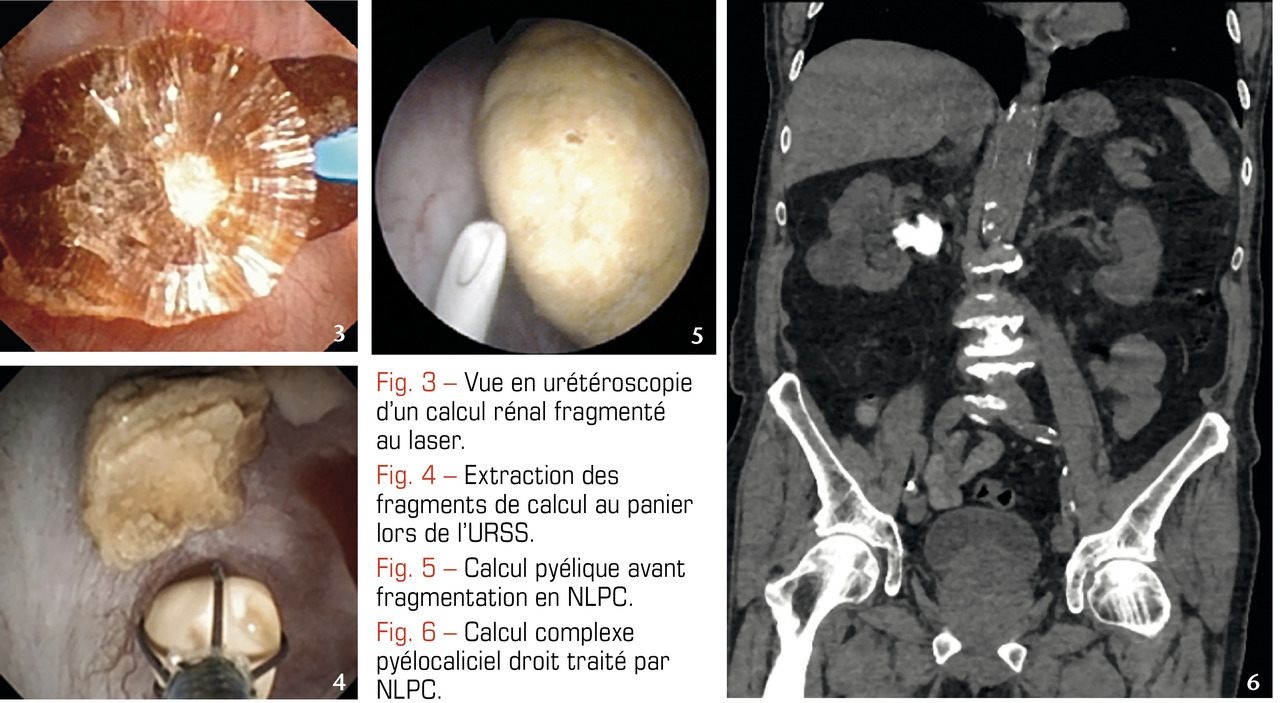

L’URS est réalisée avec des urétéroscopes métalliques de 2-3 mm de diamètre permettant d’accéder à l’uretère. L’URSS est pratiquée avec des urétéroscopes souples, fibrés ou numériques, de moins de 3 mm de diamètre atteignant les cavités rénales par voie rétrograde afin d’extraire le calcul à la pince. Associées à la fragmentation par laser, elles sont très efficaces sur ceux de moins de 2 cm, quelles que soient leur composition et leur densité au scanner (fig. 3 et 4).2-6 En effet, aucun ne résiste à l’application intracorporelle d’un laser, même si ceux dont la taille avoisine les 2 cm requièrent parfois 2, voire 3 séances. Un drainage par sonde JJ est souvent laissé en place en post-opératoire.